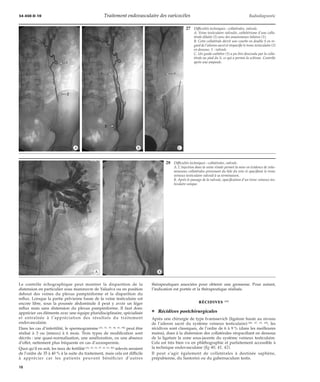

34 Technique de traitement. Après mise en place d’un ressort (2) et injection d’une

première ampoule de sclérosant, la sonde (1) est en partie retirée de façon à scléroser

plus haut le système veineux testiculaire.

32 Technique de traitement. La sonde a été descendue bas en regard de l’épine sciatique.

Le tronc veineux testiculaire sus-jacent n’est pas visible, suite à un spasme sur la sonde.

33 Technique de traitement. Position respective de la sonde et des ressorts (flèche)

après leur largage.

35 Technique de traitement. Il existait deux branches importantes au niveau pelvien,

on a d’abord placé dans la première branche cathétérisée un ressort (flèche) ; puis la

sonde a été descendue bas dans le tronc principal pour la sclérose.